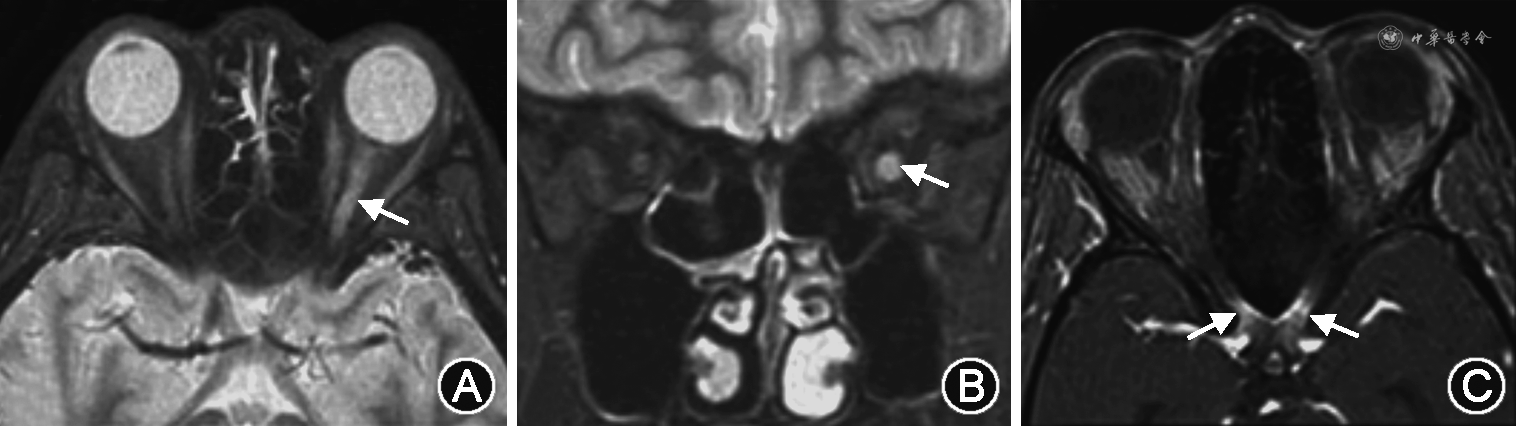

1.视神经炎:最易累及视神经后段和视交叉,病变节段可大于1/2的视神经长度。急性期可见视神经增粗、强化,部分伴视神经鞘强化。慢性期表现为视神经萎缩,形成双轨征(图1A~C)。